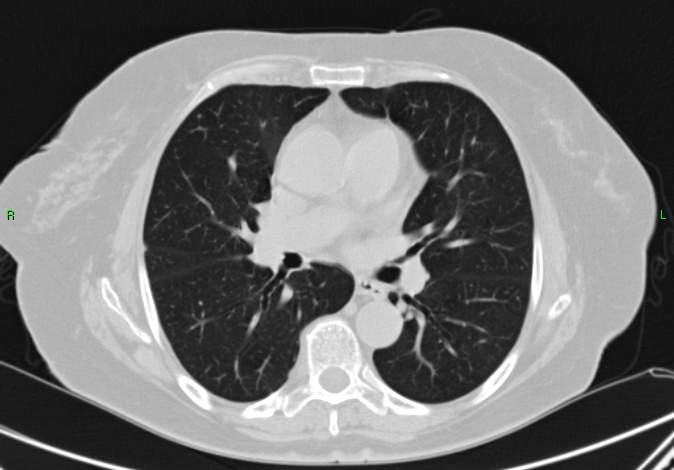

3b: Multiple lung metastasis, CT lung window (axial, coronal reformat)

3c, coronal reformat

70 year old man, colon tumor.

Radiograph: Bilateral extensive, confluating patchy-nodular shadowing with diffuse reticular pattern. The diaphragm contour is partially blurry bilaterally: lymphangiosis carcinomatosa.

CT: Numerous 1-6 cm round and irregular, lobulated-spiculated contrast enhancing lesions in both lungs, everywhere sporadically.